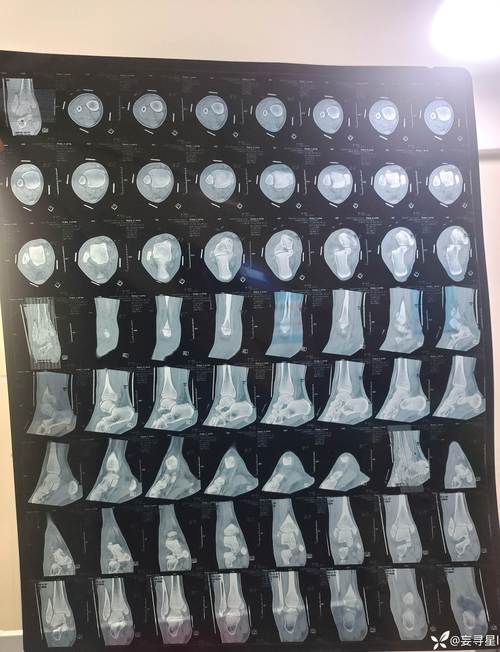

在第29轮意甲联赛,尤文客场1-0战胜乌迪内斯。比赛第49分钟K·图拉姆因伤被换下。意大利天空体育表示,K·图拉姆是在上半场右脚踝受伤,但他依然坚持踢完了上半场,并在中场休息时检查过身体状况,认为自己可以在下半场继续比赛。但下半场只踢了4分钟,K·图拉姆就无法再坚持,只得被库普梅纳斯换下。接下来K·图拉姆将接受进一步详细检查。